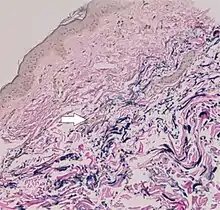

Histopathology of PXE-like papillary dermal elastolysis: Loss of elastic fibers in the papillary dermis and abnormal pattern in the reticular dermis (arrow)[28]

Pseudoxanthoma elasticum versus histopathological differential diagnoses

on light microscopy (LM) and electron microscopy (EM)[28]

Pseudoxanthoma elasticumLM: Mid-dermal calcification and fragmentation of elastic fibers

EM: Mineralization in elastic fiber core

PXE-like disease with coagulation deficiencyLM: Middermal calcification and fragmentation of elastic fibers

EM: Mineralization in elastic fiber periphery

HemoglobinopathiesLM: Middermal calcification and fragmentation of elastic fibers

PXE-like papillary dermal elastolysisLM: Selective elastic tissue elimination in the papillary dermis and presence of melanophages